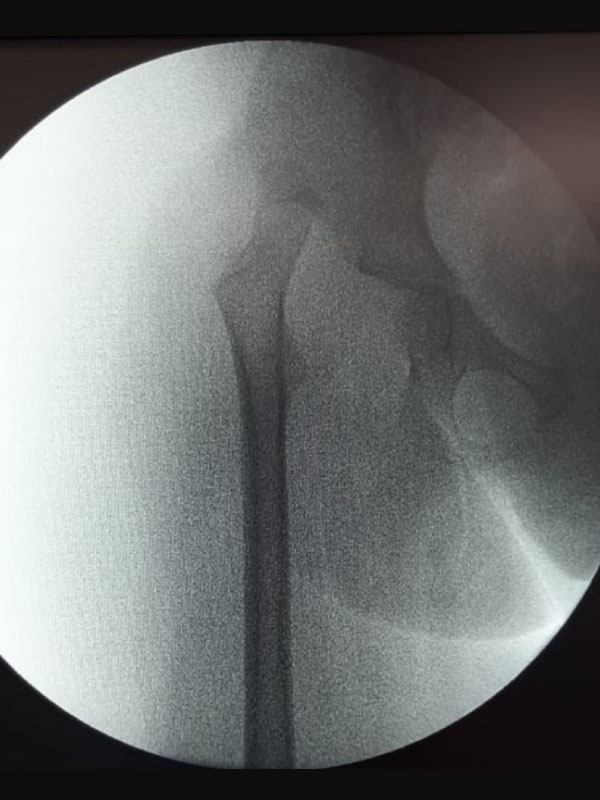

Caso No. 7 - Displasia de cadera derecha y síndrome down

Paciente femenino de 4 años de edad. Rx preoperatoria

Transoperatoria de Acetabuloplastia

Diagnóstico: Síndrome de Down con Displasia de cadera derecha con luxación.

Posoperación luego de la reducción abierta

Tratamiento quirúrgico realizado: Rx posoperatoria luego de la reducción abierta, acetabuloplastía y acortamiento femoral.